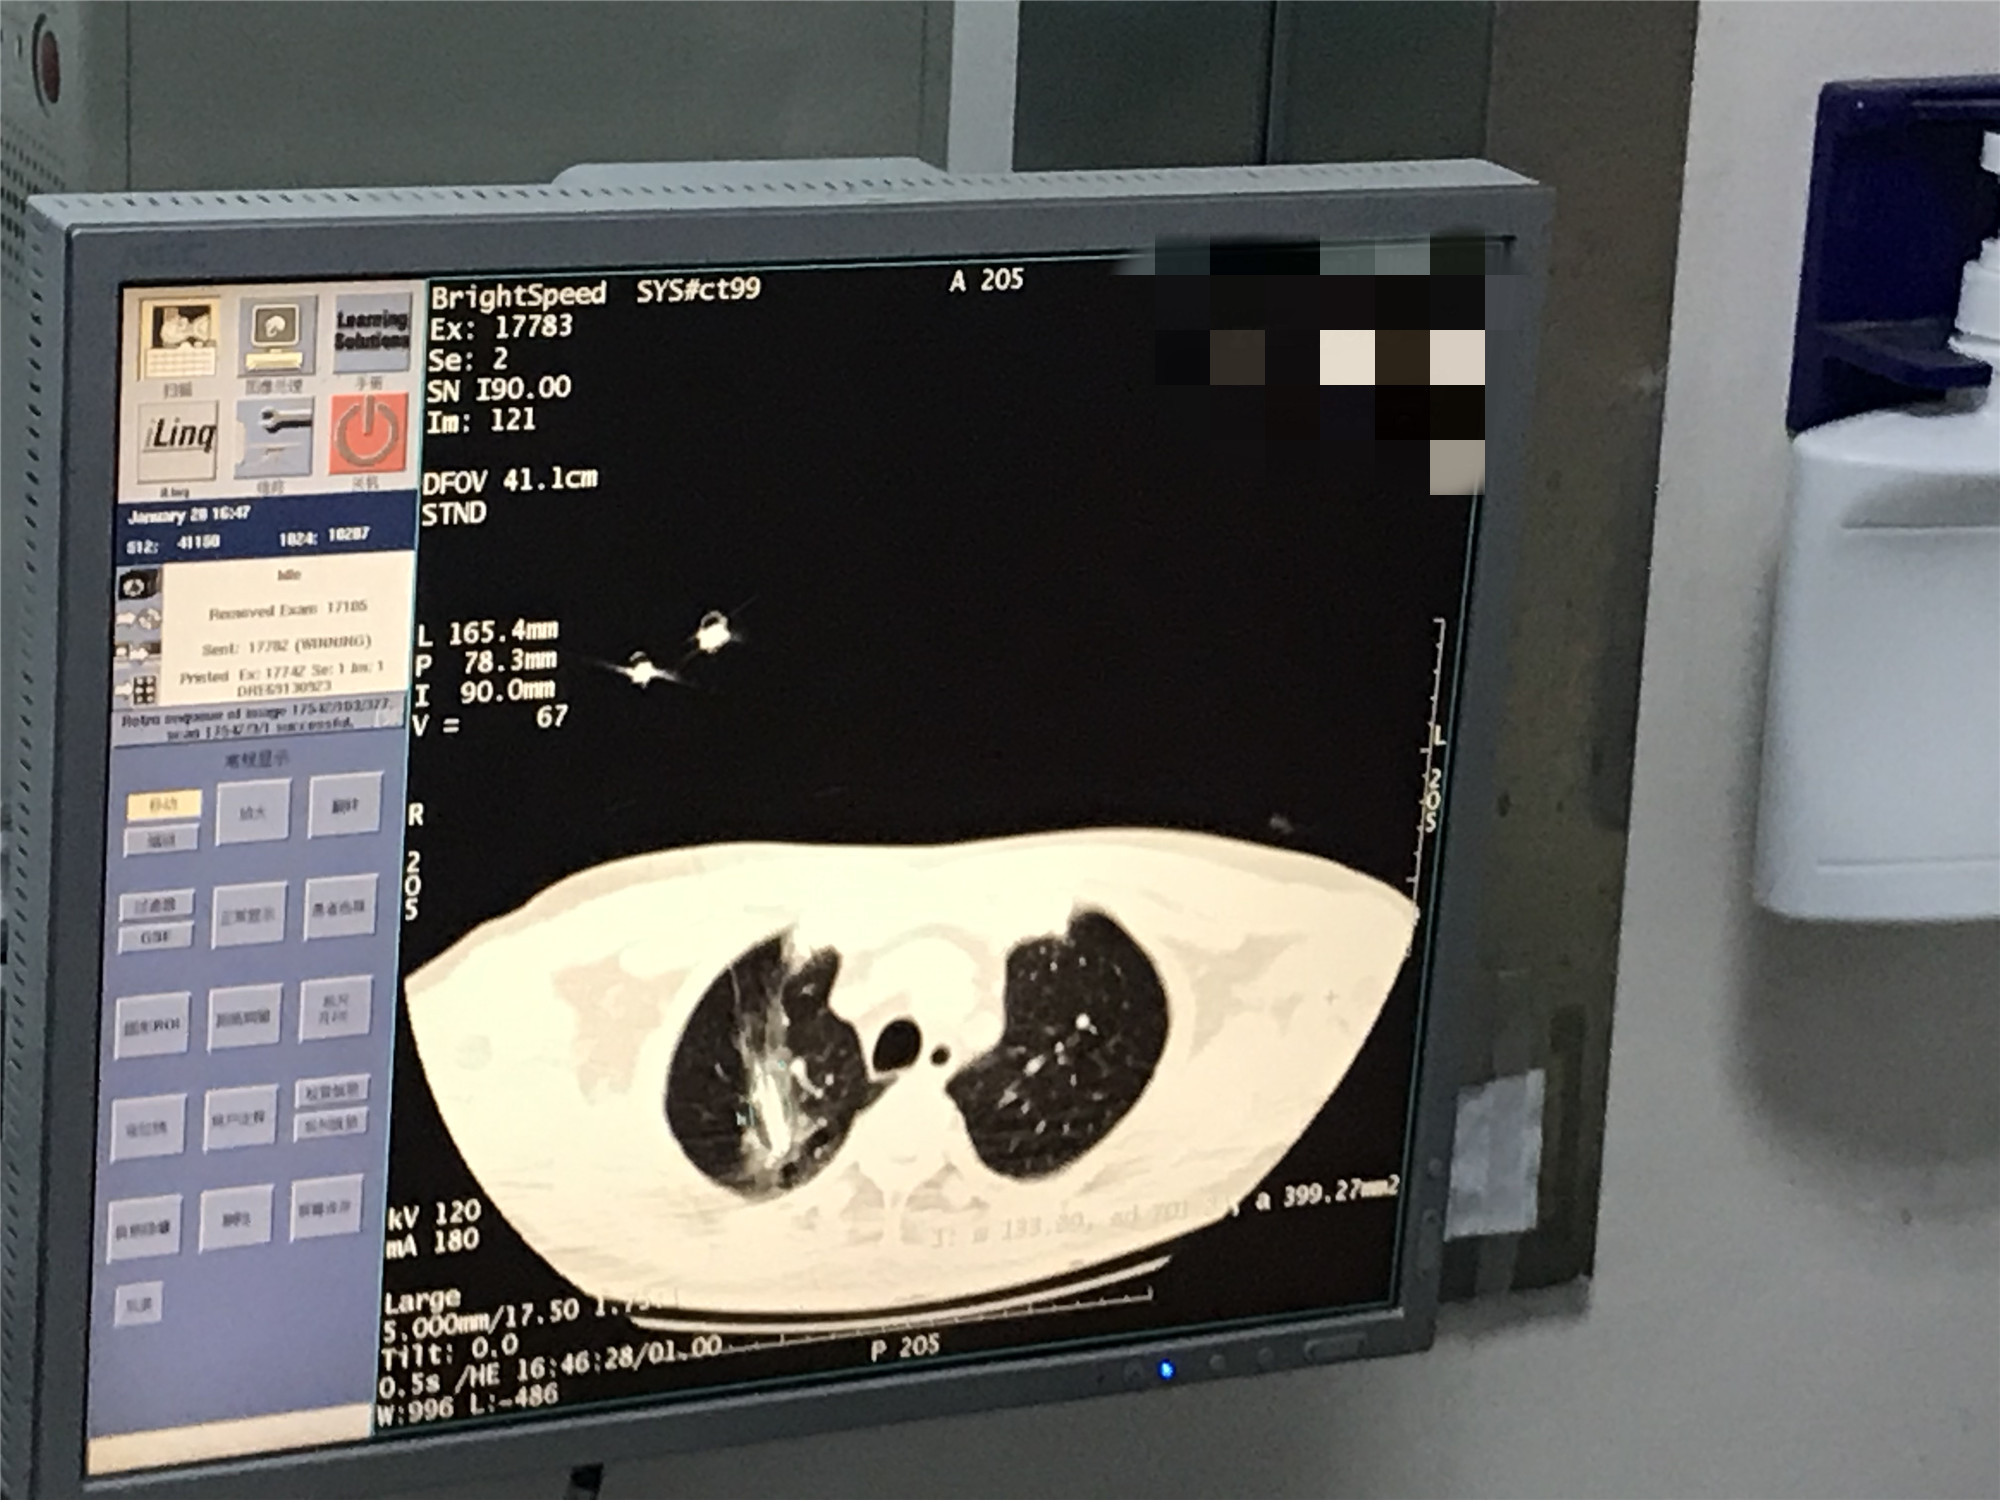

2021年1月份肺部氩氦刀手术